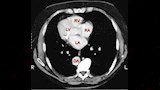

في أروقة مختبرات المستشفيات وعدسات الأطباء داخل أقسام الطوارئ، ظهرت نتائج تحاليل طبية وصفت بـ"الخارجة عن المألوف"، بعضها وصل حد الصدمة لما يحمله من أرقام غير قابلة للتصديق، وهذه الحالات، رغم ندرتها، تبقى بمثابة لغز يستفز العقل ويزيد من شأن المتابعة الطبية الاحترافية.

أغرب نتيجة تحليل

"أغرب نتيجة تحليل رأيتها في حياتي".. بهذه الكلمات وصف أحد مراكز التحاليل الطبية عبر "فيسبوك" حالة غريبة وردتهم من مريض أرسل صورة نتيجة فحصه طالبًا تفسيرها، وسط حالة من الارتباك والدهشة، إذ بدت الأرقام غير منطقية وغير قابلة للفهم.

وما زاد من غرابة الموقف أن الطبيب المعالج شخص الحالة على أنها إصابة بفيروس كورونا، رغم أن مؤشرات التحليل لا تحمل أي دلالة واضحة على ذلك، وفق ما أفاد المركز.